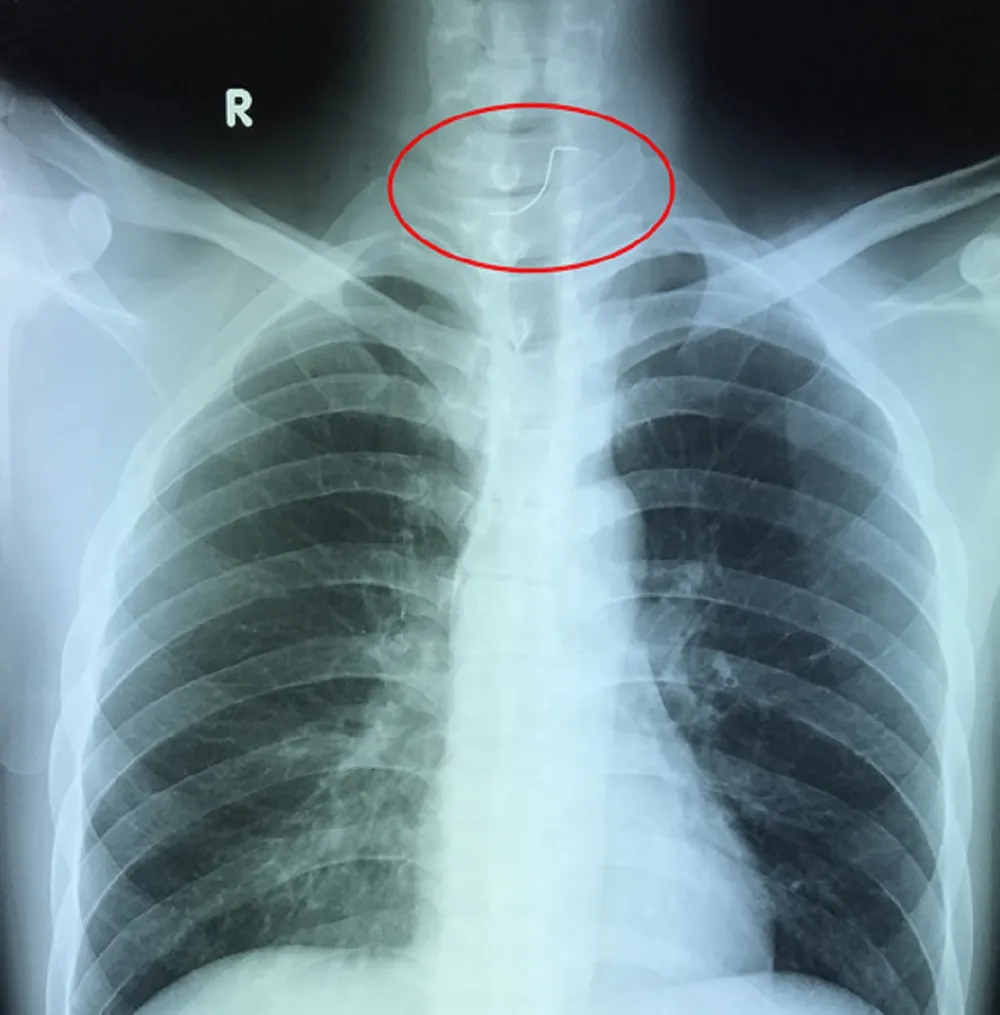

Ảnh chụp X-quang của bệnh nhân P. Ảnh: HP

Theo TS-BS Nguyễn Văn Châu, sau khi chụp X-quang, các bác sĩ đã xác định bệnh nhân P. bị một dị vật mắc ở thực quản. Ngay lập tức các bác sĩ đã tiến hành nội soi gắp ba chiếc răng giả ra khỏi thực quản của bệnh nhân.